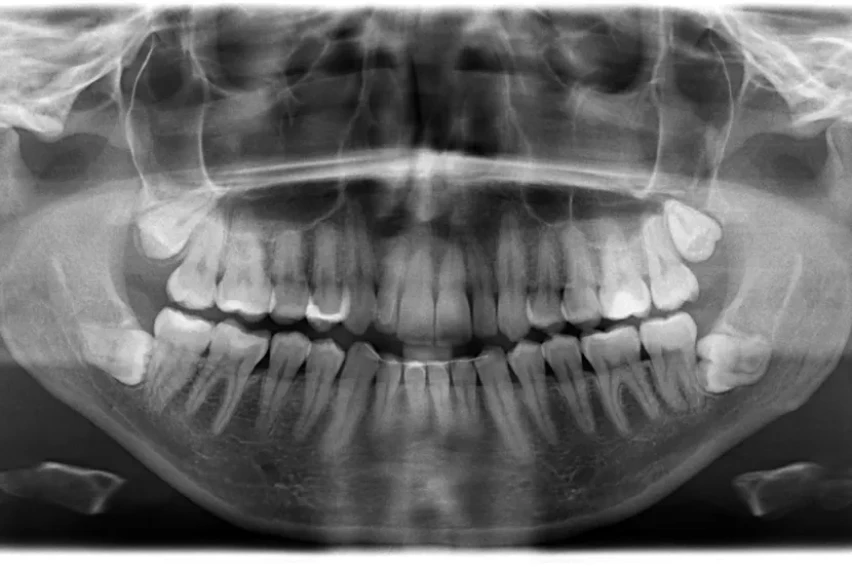

Меѓутоа подоцна рендгенската снимка на забите покажала дека постоеле уште четири заби што требало да изникнат.

„На почетокот од 2023 година сфатив дека имам вкупно 42 заби. За среќа повеќето заби пораснале право и без никакви компликации“, раскажал Мунианди.

Исто така тој споделил дека стоматолозите кои ги прегледувале неговите заби за Гинисовата книга на рекорди (Guinness World Records) му соопштиле уште една изненадувачка вест – има уште два заби кои допрва треба да изникнат. Тој официјално ја добил титулата за најголем број заби кај мажи, додека женската верзија на рекордот ја држи Калпана Балан од Индија која има 38 заби.